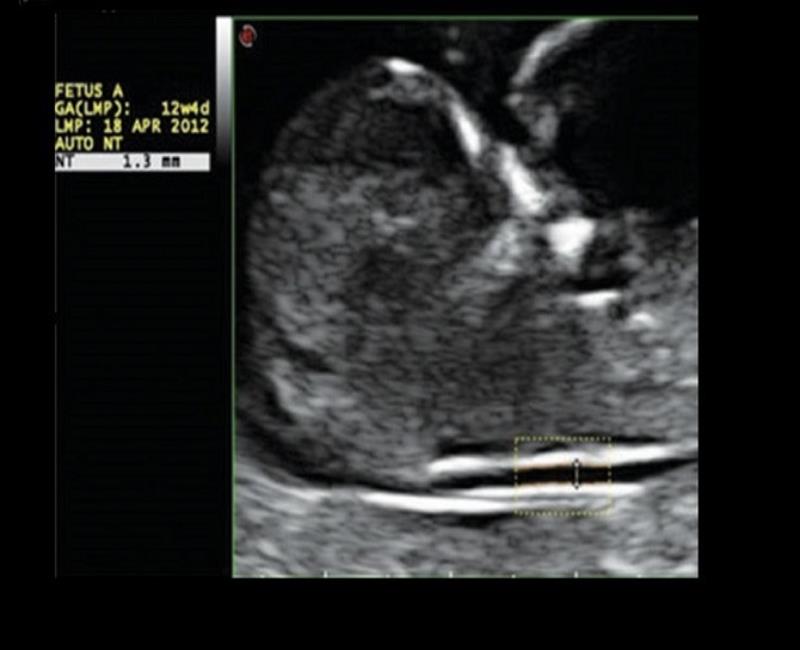

AutoNT – Tự động đo độ mờ da gáy.

may sieu am mylab x7

Nhờ nền tảng Windows 10 mạnh mẽ, MyLab X7 giúp giảm thời gian kiểm tra và quy trình làm việc tốt hơn nhờ nhiều chức năng xử lý "không cần nhấp chuột" tự động để chụp ảnh, doppler, xử lý hậu kỳ, đo lường, lưu trữ và kết nối.Với quy trình xử lý “không cần nhấn”, phân suất tống máu của tim, độ mờ da gáy của thai nhi... giờ đây có thể được thực hiện nhanh chóng và dễ dàng.